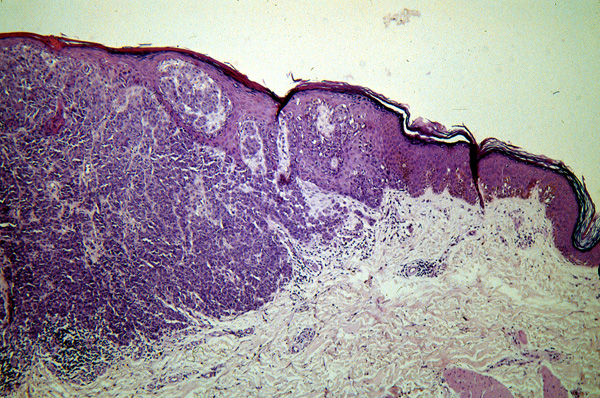

Vertical growth phase melanoma =مرحلة نمو الميلانوما عموديا